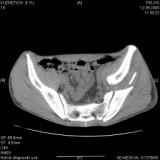

Уважаемые коллеги! Хотелось бы услышать совет по тактике лечения представлленого больного.

Поступил после лечения в одном изотделений области. Травма 2,5 месяца назад.

После выведения

из шока был произведен остеосинтез перелома бедра, предплечья, до перевода к нам проводилось

вытяжение по оси шейки бедра за стержень, введенный в большой вертел. На сегодня деформация

ригидна, клинически мобильности не определяется.